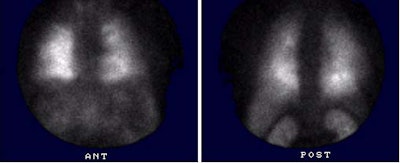

(Case submitted by Dr. Marc Cote, D.O.)The middle aged male patient with end-stage liver disease shown below complained of increasing shortness of breath and had an A-A gradient on arterial blood gas analysis. A ventilation-perfusion scan was performed to exclude pulmonary embolism.

The Tc-MAA exam demonstrated heterogeneous pulmonary perfusion and the presence of right to left shunting as evidenced by renal, hepatic, splenic, and cerebral activity. The findings and clinical history were considered diagnostic of hepatopulmonary syndrome.